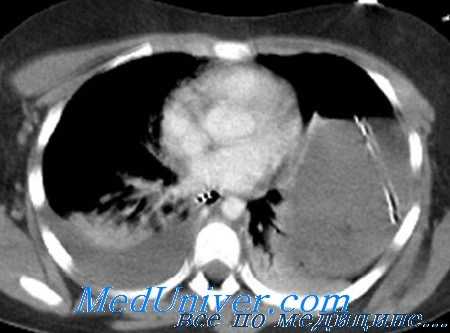

В-третьих, несмотря на доступность КТ и ее незаменимую роль в лечении закрытых повреждений паренхиматозных органов, существуют и ограничения. Авторы хорошо проиллюстрировали ненадежность метода для диагностики повреждений полых органов или брыжеек. Типичные косвенные признаки повреждений включают свободную жидкость без повреждения паренхиматозного органа, «затемнение» или «штриховку» брыжейки и утолщение кишки.

Трудность в диагностике повреждений кишки снова напоминает клиницисту о важности клинического обследования. Пациенты с усиливающейся болью, развивающимся перитонитом, гипертермией, не разрешающейся тахикардией и увеличением лейкоцитоза или амилазы в крови нуждаются в решении об оперативной ревизии. Очень сложно решить клиническую дилемму пациентов, которых невозможно обследовать.

Наиболее распространенным показанием к лапаротомии у этих пациентов, особенно с тяжелой ЧМТ, является свободная жидкость, выявленная при КТ без повреждения паренхиматозного органа. Другим диагностическим выбором у этих пациентов, кроме лапаротомии, может быть ДЛБП, чтобы определить количество лейкоцитов и ферментов.

В-четвертых, эффективность лапароскопии при травме ограничена. Большинство операций при травме носит экстренный характер, тем самым препятствуя ее использованию. Кроме того, при лапароскопии ограничено полное обследование кишки на предмет маленьких повреждений, особенно у больных с колотыми ранами и возможными сквозными ранениями тонкой кишки.